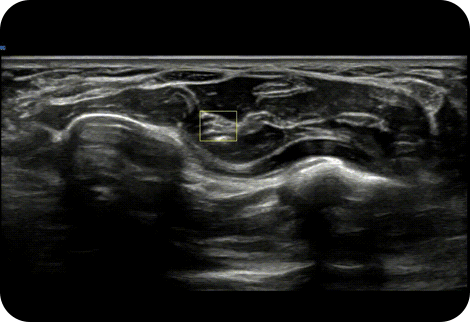

Display needle tip clearly

NeedleMate+™ ¹ delineates needle location when performing interventions such as nerve blocks. Improved accuracy and efficiency in procedure are possible with beam steering added to NeedleMate+™.